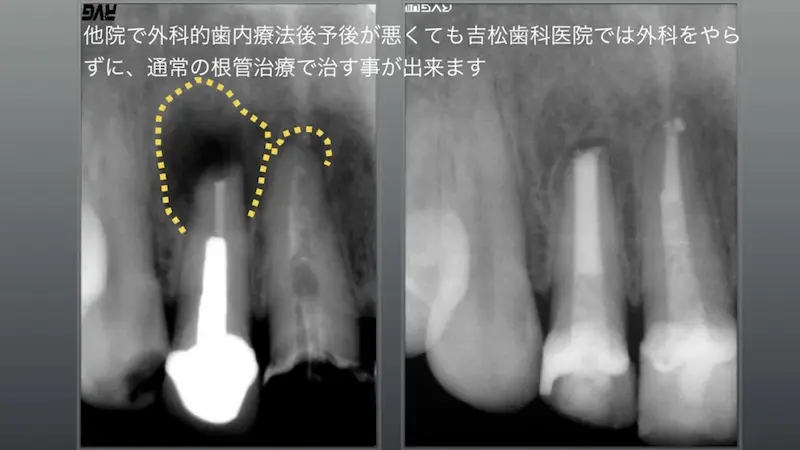

外科的歯肉療法後予後が悪くても

通常の根管治療で治すことができます

他院で以前、外科的歯内療法をを行ったが予後が悪く、虎ノ門吉松歯科医院に来院。

長くて太いメタルポスト(レントゲン上では白い部分)が確認でき、別な歯科医院では長いメタルポストは取れないと言われて来院、術前黄色の点線部分は大きく骨が吸収して、口腔内では時々腫れを繰り返す症状があるとのこと。

通常の根管治療を2回行い、数ヶ月後には骨再生がレントゲン上で現れ、外科をやらなくても通常の根管治療で虎ノ門吉松歯科医院では治す事が可能です。